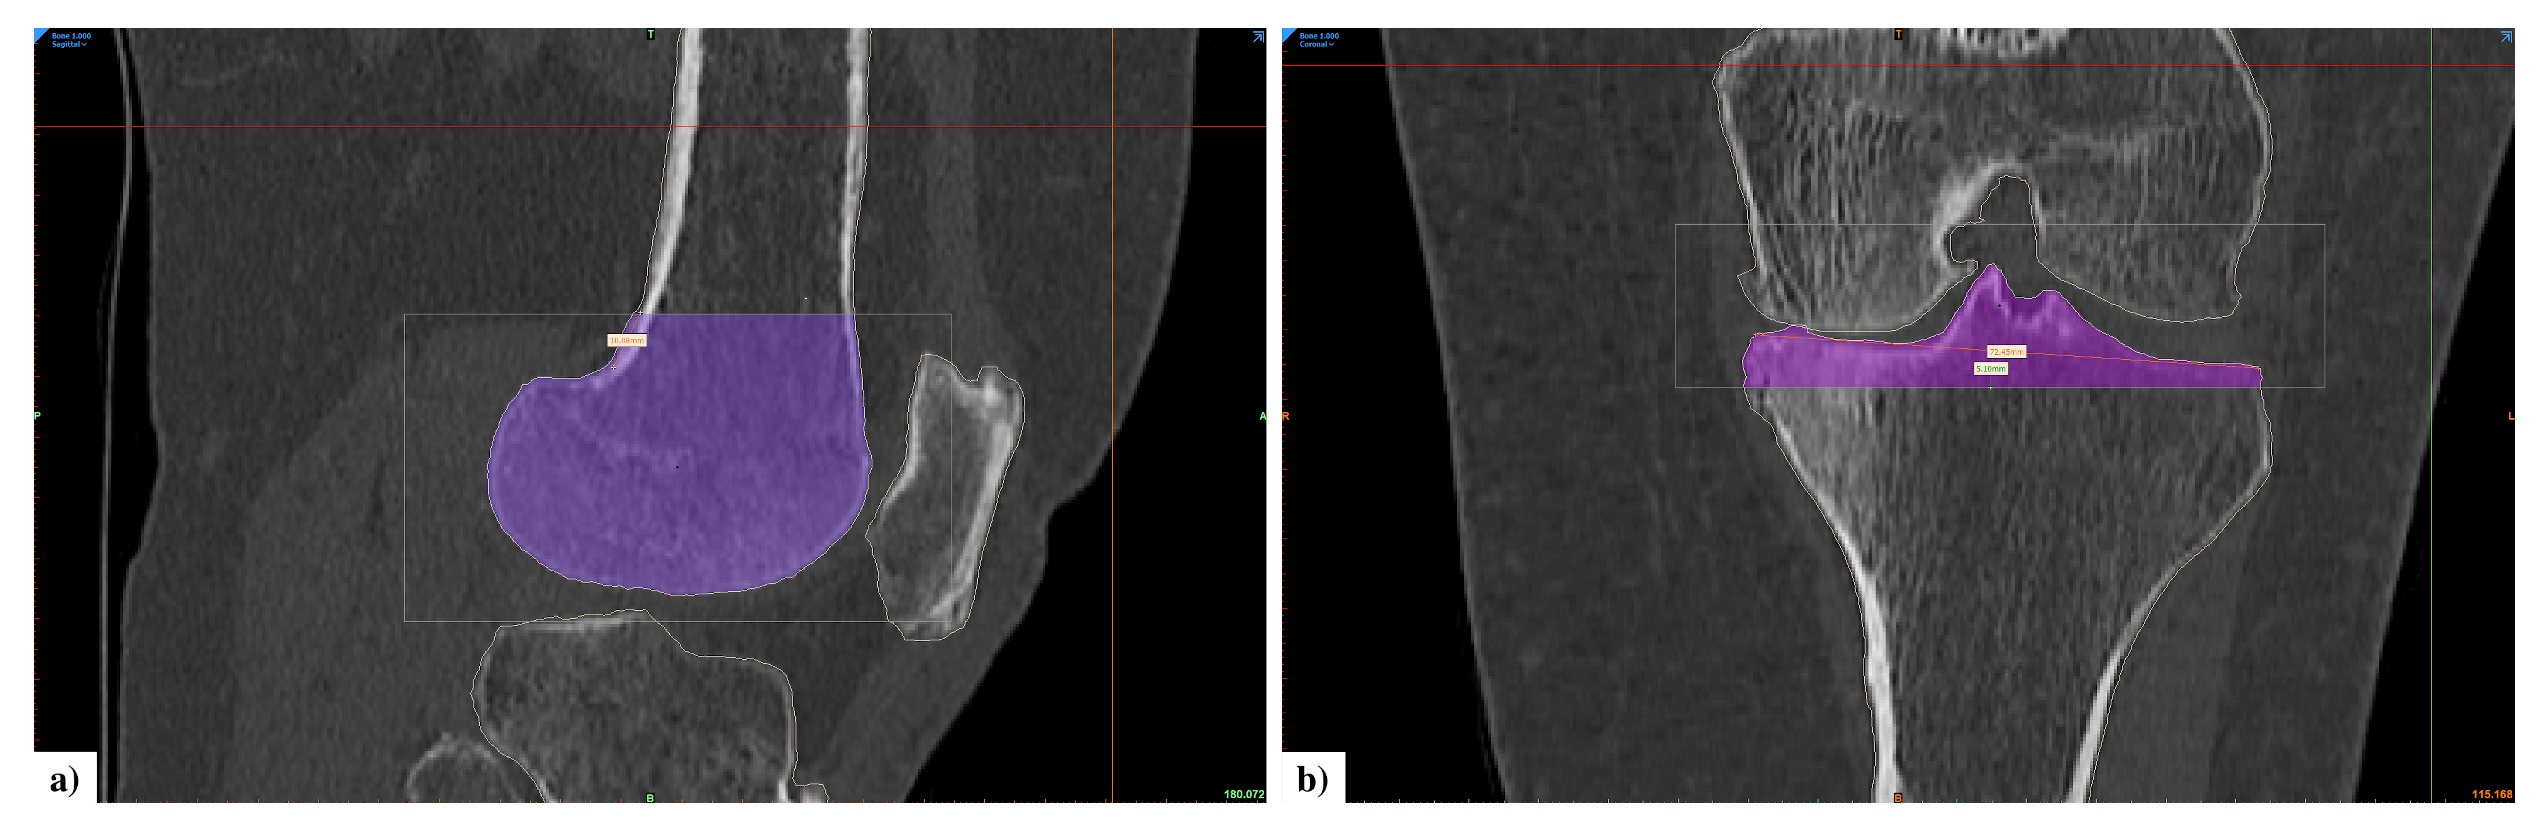

2.2.1. Segmentation

2.2.2. Wall Thickness and Curvature Analysis